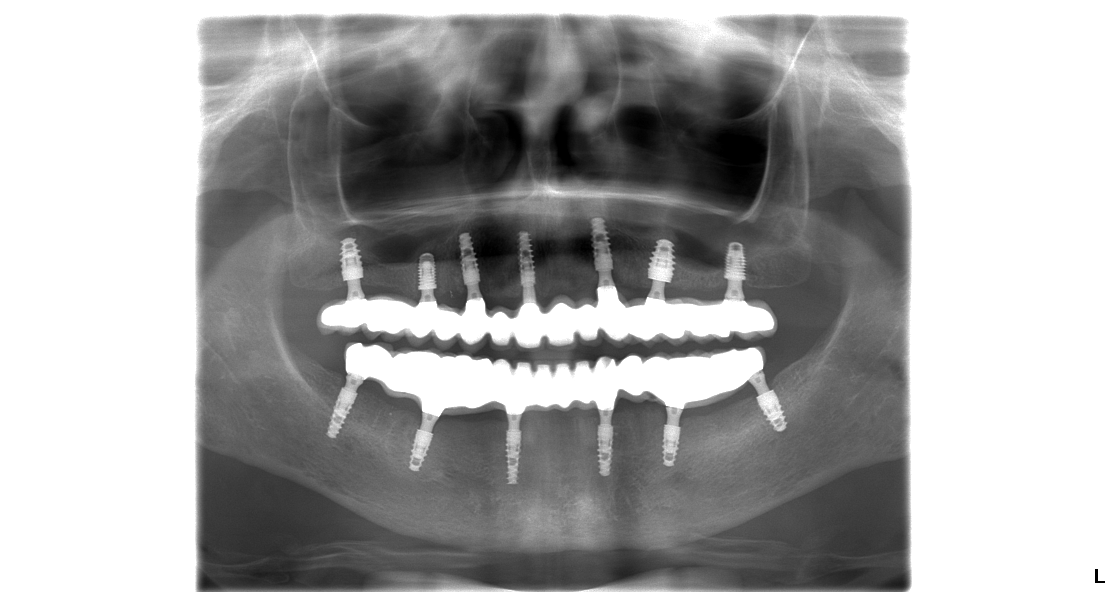

V prípade pána Tomáša bolo potrebných 6 zubných implantátov vo vrchnej a 6 zubných implantátov v spodnej čeľusti na ktoré sa nasadili 14 – členné keramické mostíky. U pni Márie bolo potrebných 7 zubných implantátov vo vrchnej čeľusti a 6 zubných implantátov v spodnej čeľusti.

Snímok pani Márie po dokončení ošetrenia